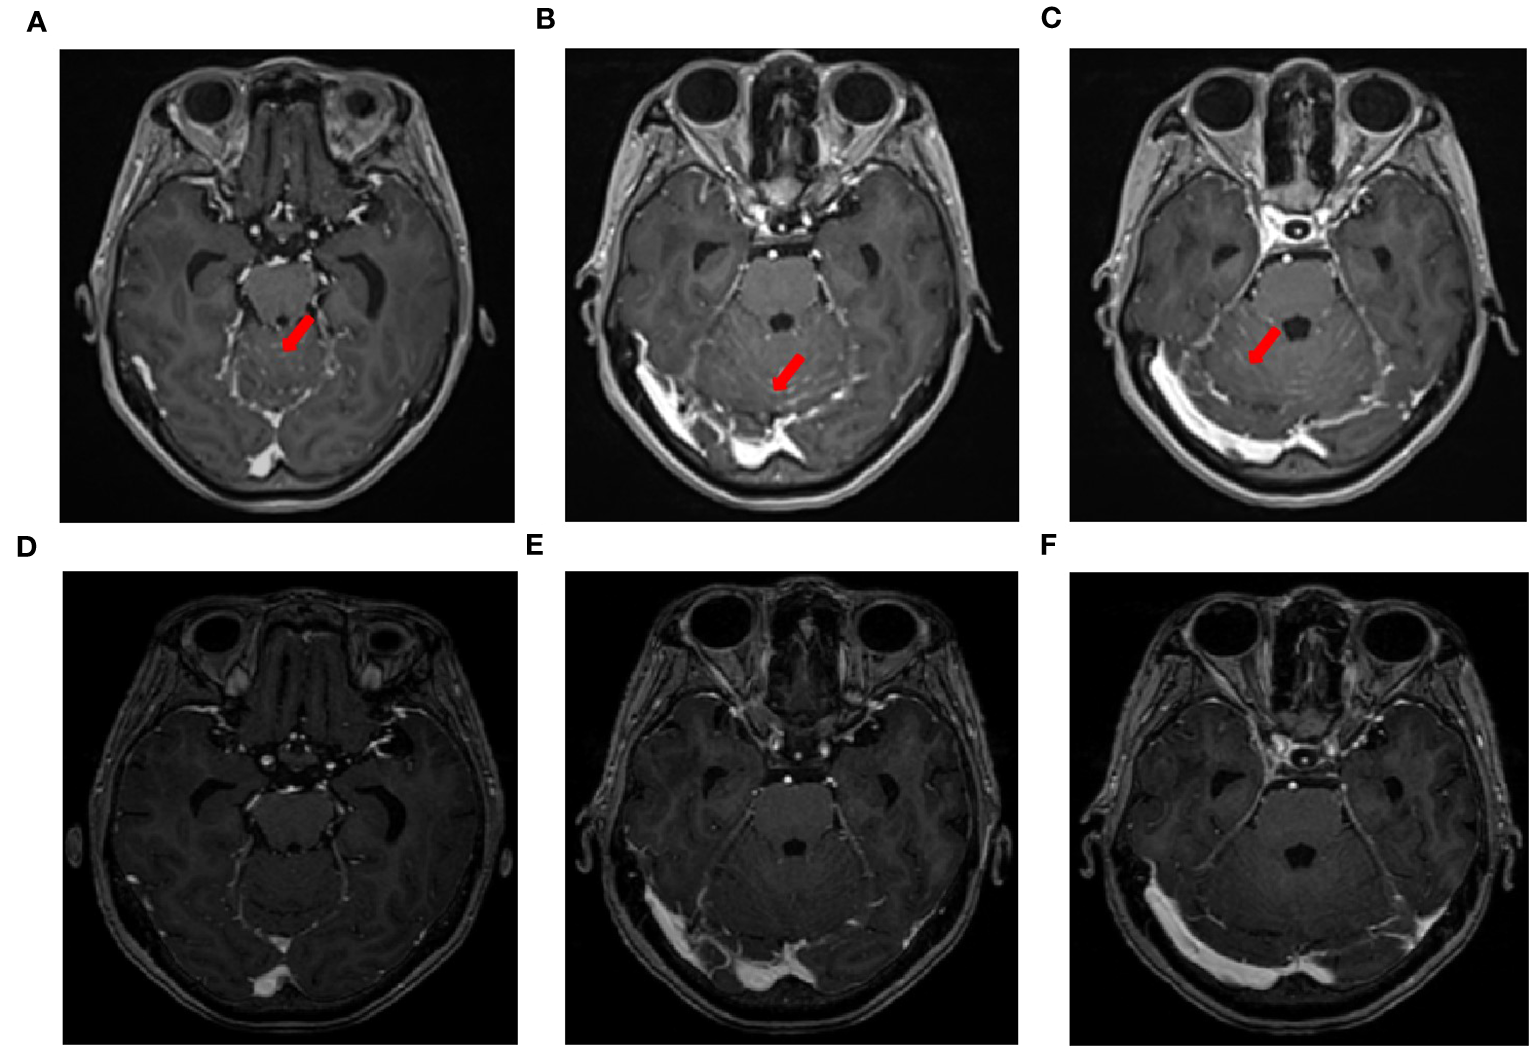

A 71-year-old male, with a smoking history of over 40 years, was admitted to The First Affiliated Hospital of Gannan Medical University (Ganzhou, China) on October 16, 2016, with a persistent cough lasting for 9 months and hemoptysis for 1 week. CT revealed a mass in the upper lobe of the left lung. On October 20, 2016, the patient underwent a total resection of the left lung and systemic lymph node dissection under general anesthesia. Postoperative pathology revealed lung adenocarcinoma, and one-third of the hilar lymph node metastases was positive. Immunohistochemistry revealed TTF-1 (+), CK7 (+), Napsin A (+), and Ki-67 expression (approximately 20%). The postoperative diagnosis was stage IIA (pT1bN1M0), according to the 7th edition of the TNM classification for lung cancer. Genetic testing using ARMS revealed the EGFR21 L858R mutation. After surgery, the patient received four cycles of adjuvant chemotherapy with docetaxel and cisplatin. On July 23, 2019, the patient presented with headache and pain in the neck and chest. MRI and CT scans indicated metastases in the T1 and T6 vertebrae (Figures 1A, B). Subsequently, the patient underwent radiotherapy for vertebral metastases at a dose of 30 Gy/10 fx along with molecular-targeted therapy using gefitinib (Iressa, 250 mg/day). During regular follow-up examinations, the disease remained stable, with osteogenic changes observed in the thoracic vertebral metastases (Figures 1C, D). In May 2021, CEA levels increased from 9.7 ng/ml to 214 ng/ml, accompanied by the onset of a grade 3 rash following the oral administration of gefitinib. Consequently, target therapy was switched to osimertinib at 80 mg/day. After one month, the CEA decreased to 161.5 ng/ml and the rash improved to grade 1. In September 2021, the patient presented with dizziness, headache, nausea, vomiting, and weakness in both lower extremities. Magnetic resonance imaging (MRI) revealed significant thickening and pronounced enhancement of the meninges in the cerebellum (Figures 2A–C). A lumbar puncture confirmed the presence of cancer cells in the cerebral effusion, suggesting meningeal metastasis (Figure 3A). Second-generation CSF sequencing (OncoDrug-Seq sequencing platform: Illumina NextSeq500vaSeq) identified an EGFR21 L858R mutation with an abundance of 38% in combination with TP53 and FGFR3 mutations. Subsequently, the patient received a double dose of osimertinib (160 mg/day) for 2 months; however, there was no significant improvement in the dizziness or headache. Starting in November 25, 2021, the patient received an intrathecal injection of 30 mg pemetrexed, administered 1-2 times per week, 2-3 times per course and repeated once every 2-3 months. Additionally, the patient was prescribed one centrum tablet daily and continued targeted therapy with osimertinib (160 mg/day). Following one course of intrathecal chemotherapy, the symptoms of dizziness and headache were alleviated, and after three courses of intrathecal chemotherapy, the thickening and pronounced enhancement of the meninges in the cerebellum disappeared (Figures 2D–F), and CSF cytology was negative (Figure 3B). The patient underwent a total of 12 intrathecal injections of pemetrexed from November 2021 to November 2022. The patient has a good quality of life, and no disease progression is observed. Adverse drug reactions include grade 1 rash, grade 1 leukopenia, grade 1 thrombocytopenia, and fatigue. Considering the absence of evident neurological symptoms and negative CSF cytology, intrathecal pemetrexed chemotherapy is discontinued, and only 160 mg osimertinib targeted therapy is currently being utilized. The patient exhibites mild weakness of the lower limbs as the main clinical symptom with no apparent adverse drug reactions. Since the diagnosis of LM, the patient has survived for 28 months (Figure 4).

Figure 2

MRI changes in leptomeningeal metastasis before and after treatment. (A–C) MRI images of leptomeningeal metastasis in September 2021 showing significant thickening and pronounced enhancement of the meninges in the cerebellum. (D–F) After three courses of intrathecal chemotherapy, the thickening and pronounced enhancement of the meninges in the cerebellum disappeared.